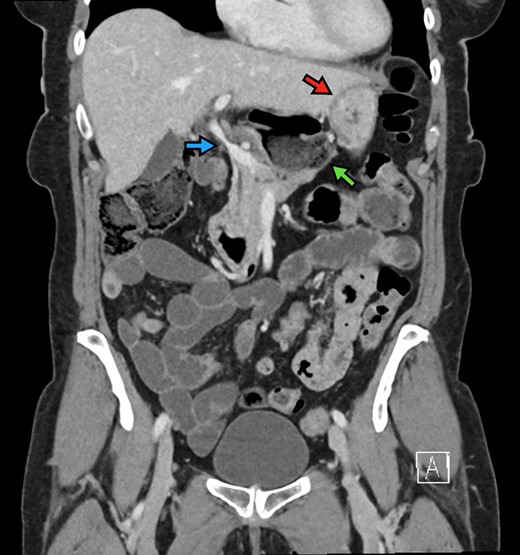

The patient is a 70-year-old woman who presented to the emergency department with acute-onset abdominal pain throughout her epigastrium for approximately 2 hours. The pain was constant and severe, extending across the bilateral upper quadrants. She had experienced pain like this once before within the past year which spontaneously resolved within 4 hours. The patient’s last oral intake was an hour before onset of the pain, and she denied any fevers, chills, nausea or vomiting. She was an otherwise healthy woman who took no medications and had no abdominal surgical history. On admission, vital signs were normal, with a heart rate in the 70’s. Although initially reported as tender by emergency department staff, after pain medication and intravenous fluids, examination by the surgical team revealed resolution of pain and a soft, non-tender abdomen. Lactic acid on presentation was 5.0 mmol/l, and her white blood cell count was 9600 µl−1, with the remainder of her laboratory values within normal limits. She underwent a computed tomography scan which demonstrated herniation of her cecum through the FoW, causing compression of the inferior vena cava (IVC) and portal vein (Figures 1–3).

Axial view demonstrating multiple air-fluid levels posterior to the liver and adjacent to the stomach (red arrow).